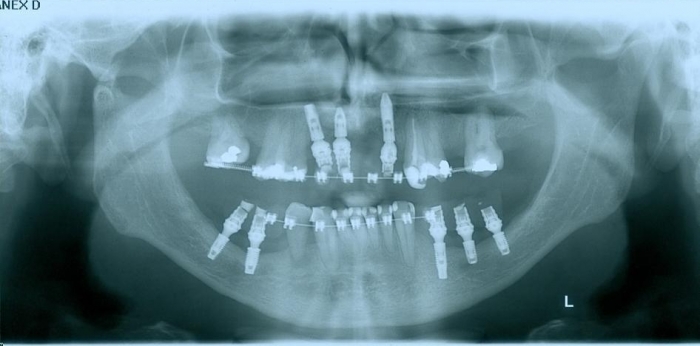

Raio - x inicial em 2009 - Clínica Cliniface

Raio - x inicial em 2009